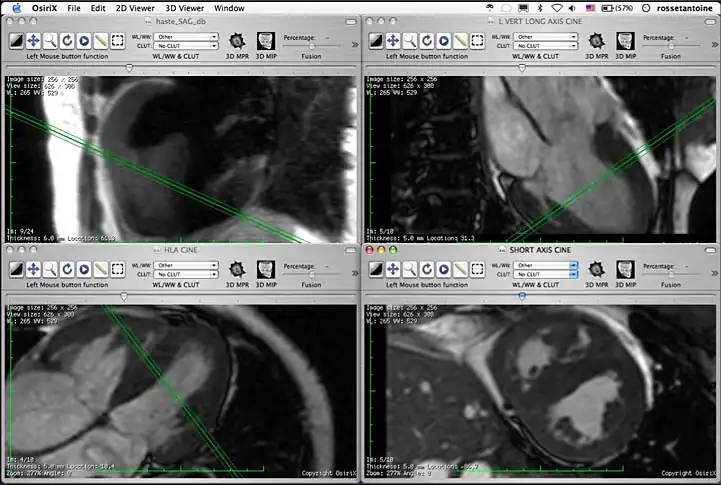

4 series opened simultaneously. Note that if all series are from the same study, you will able to see where the slice in the series you are navigating is located on the other series.